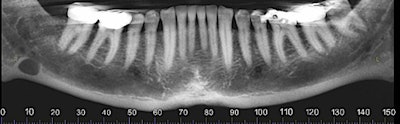

The oral surgeon ordered a cone-beam CT (CBCT) exam. Click images below to enlarge. In order: reformatted panoramic radiograph and cropped image of the area of interest, coronal view of the posterior right mandible (the inferior alveolar canal in red), and 3D reconstructed image of the posterior right mandible.

Figure 1: Reformatted and cropped panoramic film. All images courtesy of Dr. Juan F. Yepes.

Figure 2: Reformatted and cropped panoramic film.